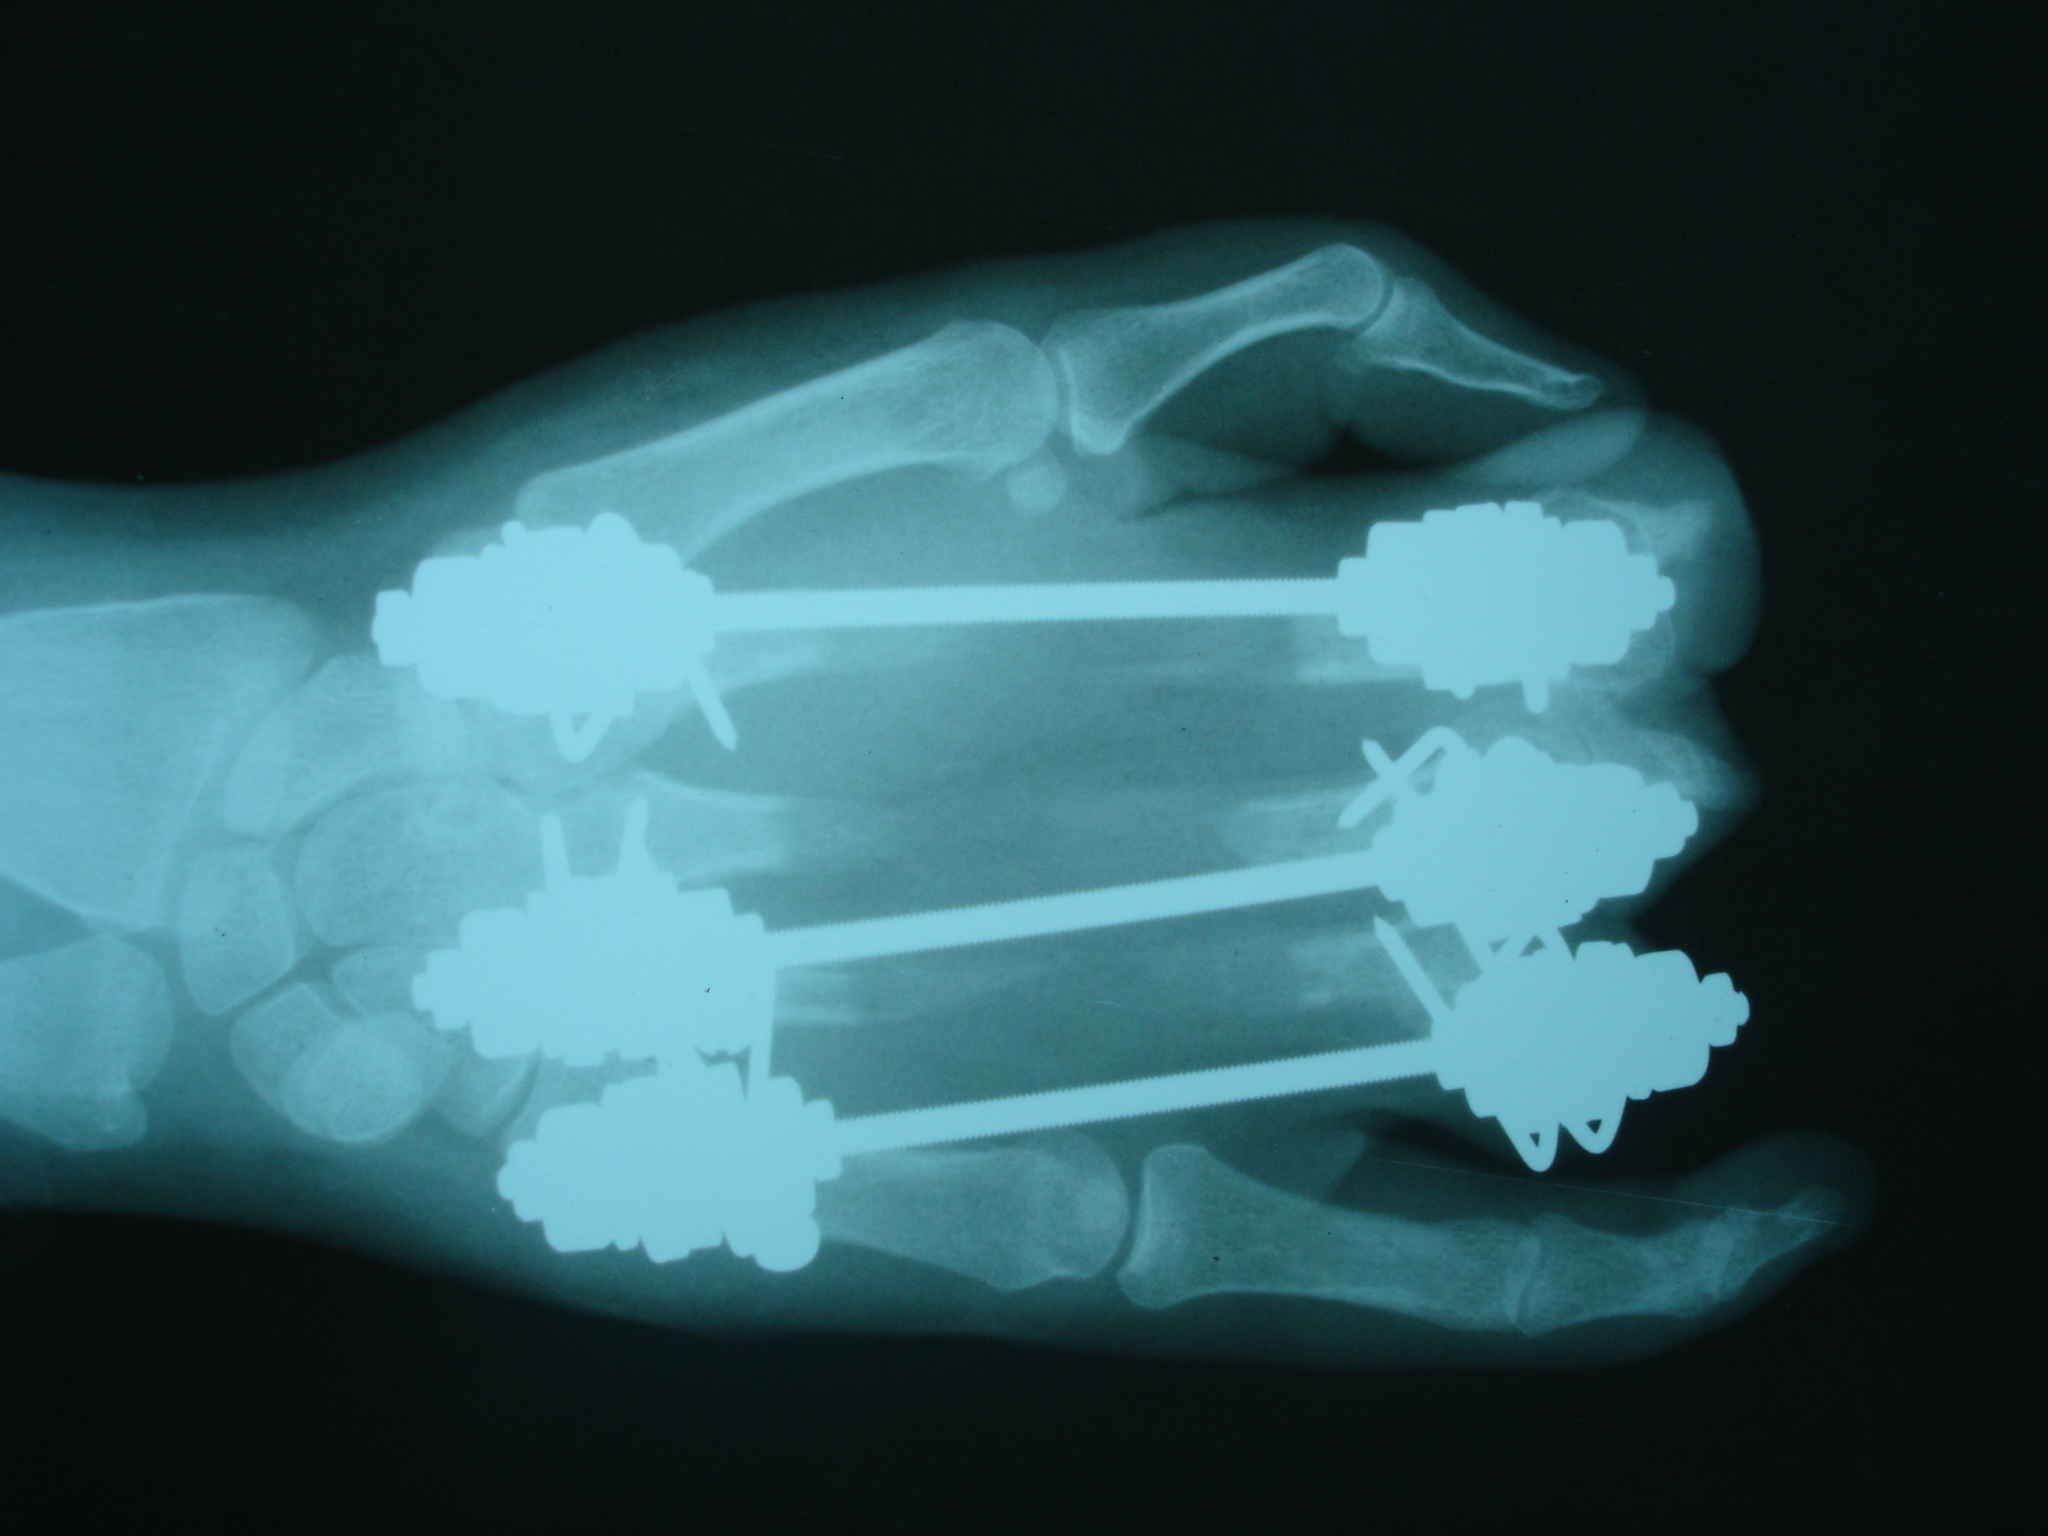

تهیه و تامین تجهیزات ارتوپدی و مشارکت در انجام اعمال جراحی ارتوپدی و عمل‌های نادر عضو تیم جراحی افزایش قد -جهت ترمیم شکستگی های قدیمی و جوش نخورده گی ها -طویل کردن اندامها- طویل کردن انگشت قطع شده - تعویض مفصل لگن _تعویض مفصل زانو _ بازسازی رباطACLوPCL_اصلاح ناهنجاریهای مادر زادی -با همکاری پزشکان و متخصصان مجرب آموزش دیده در روسیه و اتریش و سوئیس بروش جراحی ایلیزاروف و lon و lsa و واگنر و اسلایدینگ نیز جدید ترین روش افزایش قد و اندام در سال 1397 بنام hil هیل برای اولین بار- افزایش قد به 6 روش جراحی و جدیدترین روش در اروپا و روسیه. آدرس مطب _تهرانسر بلوار اصلی مجتمع سهند طبقه4 واحد 410